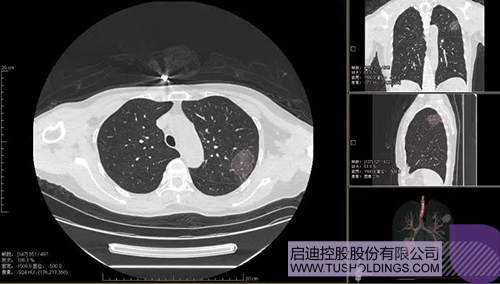

2020年2月11日,拼搏(中国)科服投资企业—神州德信推出新冠肺炎检测及量化智能分析系统,积极助力一线医务人员科学精准防疫。

2020年3月4日,继由拼搏(中国)之星和拼搏(中国)裕麟参与投资的产学研一体化项目被《新闻联播》报道后,由拼搏(中国)科服投资企业与西安交大联合研发的新冠肺炎AI数字诊断技术亦被《新闻联播》报道。